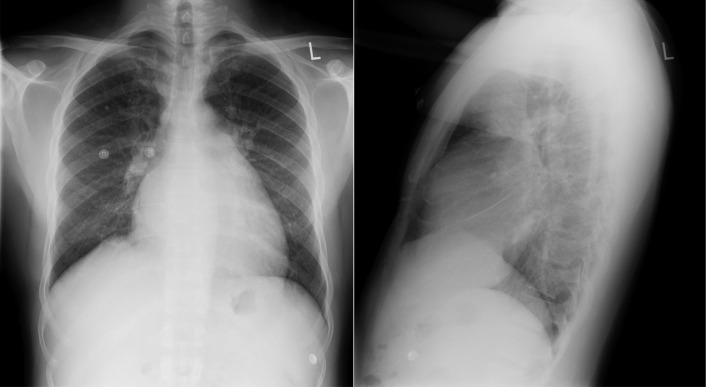

The radiographic findings of mitral stenosis ( Graphic 15-1 ; Figs. 15-1 to 15-16 ) reflect the pressure overload of the left atrium and pulmonary veins, and later of the right heart. As well, the commonly associated chronic atrial fibrillation contributes to (bi)atrial dilation. Associated rheumatic valvular lesions such as mitral regurgitation, tricuspid regurgitation, aortic insufficiency, and aortic stenosis/aortic insufficiency are common, and they alter the appearance of the heart.